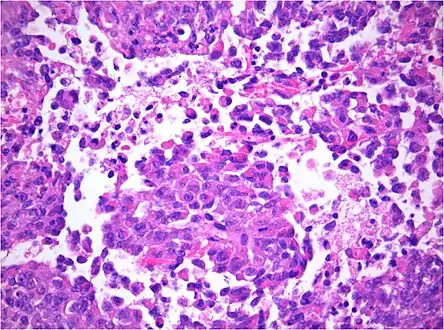

AT/RT and rhabdoid tumor share the term "rhabdoid" because under a microscope, both tumors resemble rhabdomyosarcoma.

Histology

The tumor histopathology is jumbled small and large cells. The tissue of this tumor contains many different types of cells including the rhabdoid cells, large spindled cells, epithelial and mesenchymal cells, and areas resembling primitive neuroectodermal tumor (PNET). As much as 70% of the tumor may be made up of PNET-like cells. Ultrastructure characteristic whorls of intermediate filaments are seen in the rhabdoid tumors (as with rhabdoid tumors in any area of the body). Ho and associates found sickle-shaped embracing cells, previously unreported, in all of 11 cases of AT/RT.[18]